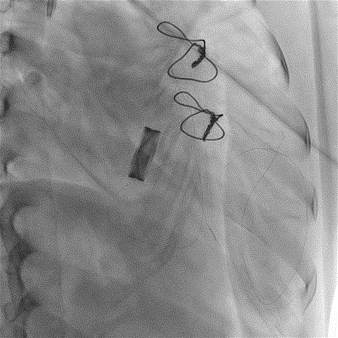

TEE, TEE and Floro showed both the leaflets to be stuck, almostno flow across the PV. The RV was higely dilated and there was severe RVdysfunction

Since TLT was not possible and surgeon refused for emergencyTranscatheter valve disruption was planned. The issues involve in the procedure were 1.Septal Puncture -due to pericardial patch in IAS, alteredanatomy due to Sx & ac dilatation of LA- Angle of puncture and Site ofpuncture. 2 Selection of wire3.Balloon- Size, make ( Compliant Vs NC), 4.Complication-like disc embolization, stuck disc leading to ac severe MA and strud fracture. The septa puncture was done as standard approach, a V18 wirewas parked in PV through a 7f Mullin sheath, Straight Turmo wire was was takenthrough a 6 JR to cross the valve and a 6 x 40 Armada balloon was dilatedacross the disc. Good acute result was obtained. The LA mean decreased from36-40 to 10-12mmHg. Post procedure the inotropic support, O2 demand decreasedover next 12 hr. However after 24 hr pt developed refractory RH failure and persistentanuria requiring SLED. And pt succumbed to the procedure 3 days after theprocedure.